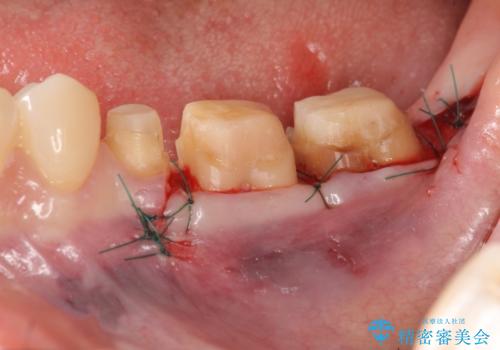

虫歯を除去すると、歯ぐきよりも深い虫歯であることが判明したため歯周外科を行い問題を解決していきます。

歯ぐきの炎症は虫歯や歯周病の再発原因となるため歯周外科による解決が望ましいです。

外科処置の注意事項(リスク・副作用など)

- 外科手術のため、術後に出血、痛みや腫れ、違和感を伴います

- 口腔内の状態によっては適応できないことがあります